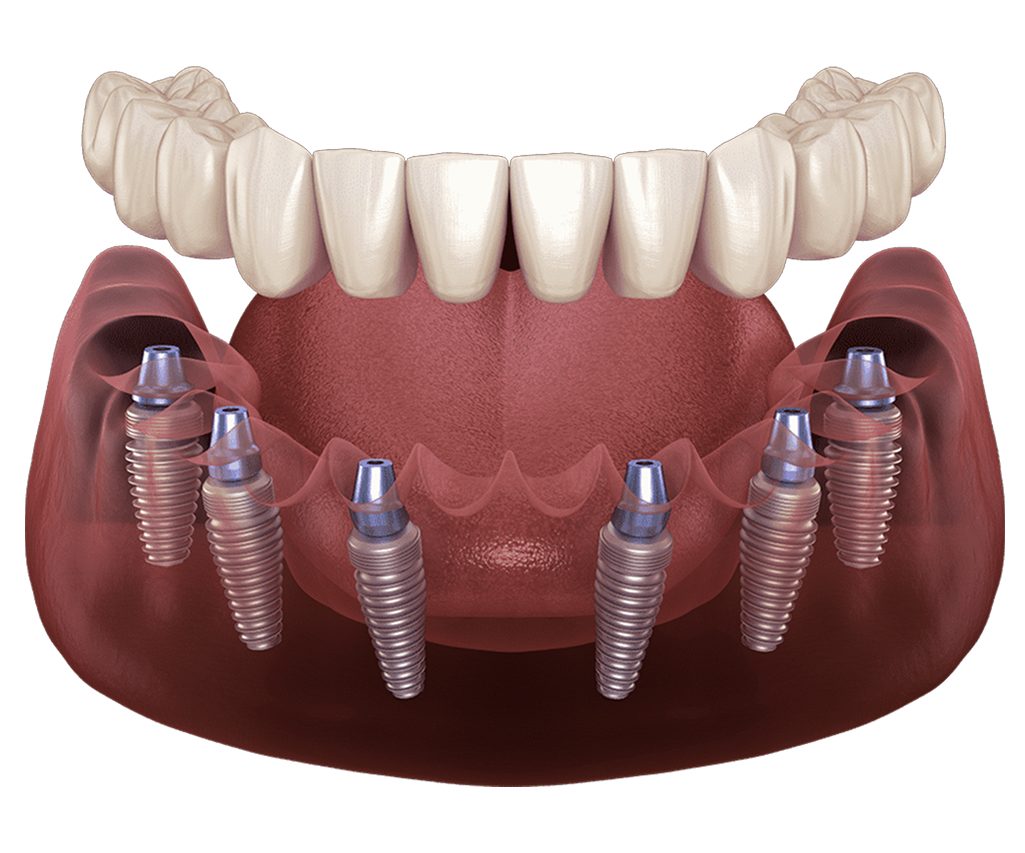

How to Determine the Most Accurate Price for All on Six Dental Implants

Achieving a precise financial roadmap for your all on six restoration

requires an understanding of the specific medical components involved.

Whether you are researching a single jaw or a full mouth restoration,

the first step is obtaining a clear unit price for the foundational

surgical phase.

Beyond the surgery, the structural system

used to fabricate your all on six prosthetic is a primary cost factor.

These advanced frameworks are classified into specialized categories

such as Titanium Bar, BioHPP Toronto, Titanium Toronto Hybrid, and CAD

CAM precision blocks. The second critical element is the selection of

the implant brand and its country of origin. Excluding professional

clinical fees, these two factors—the prosthetic type and the implant

brand—are the most significant variables determining your final

investment.